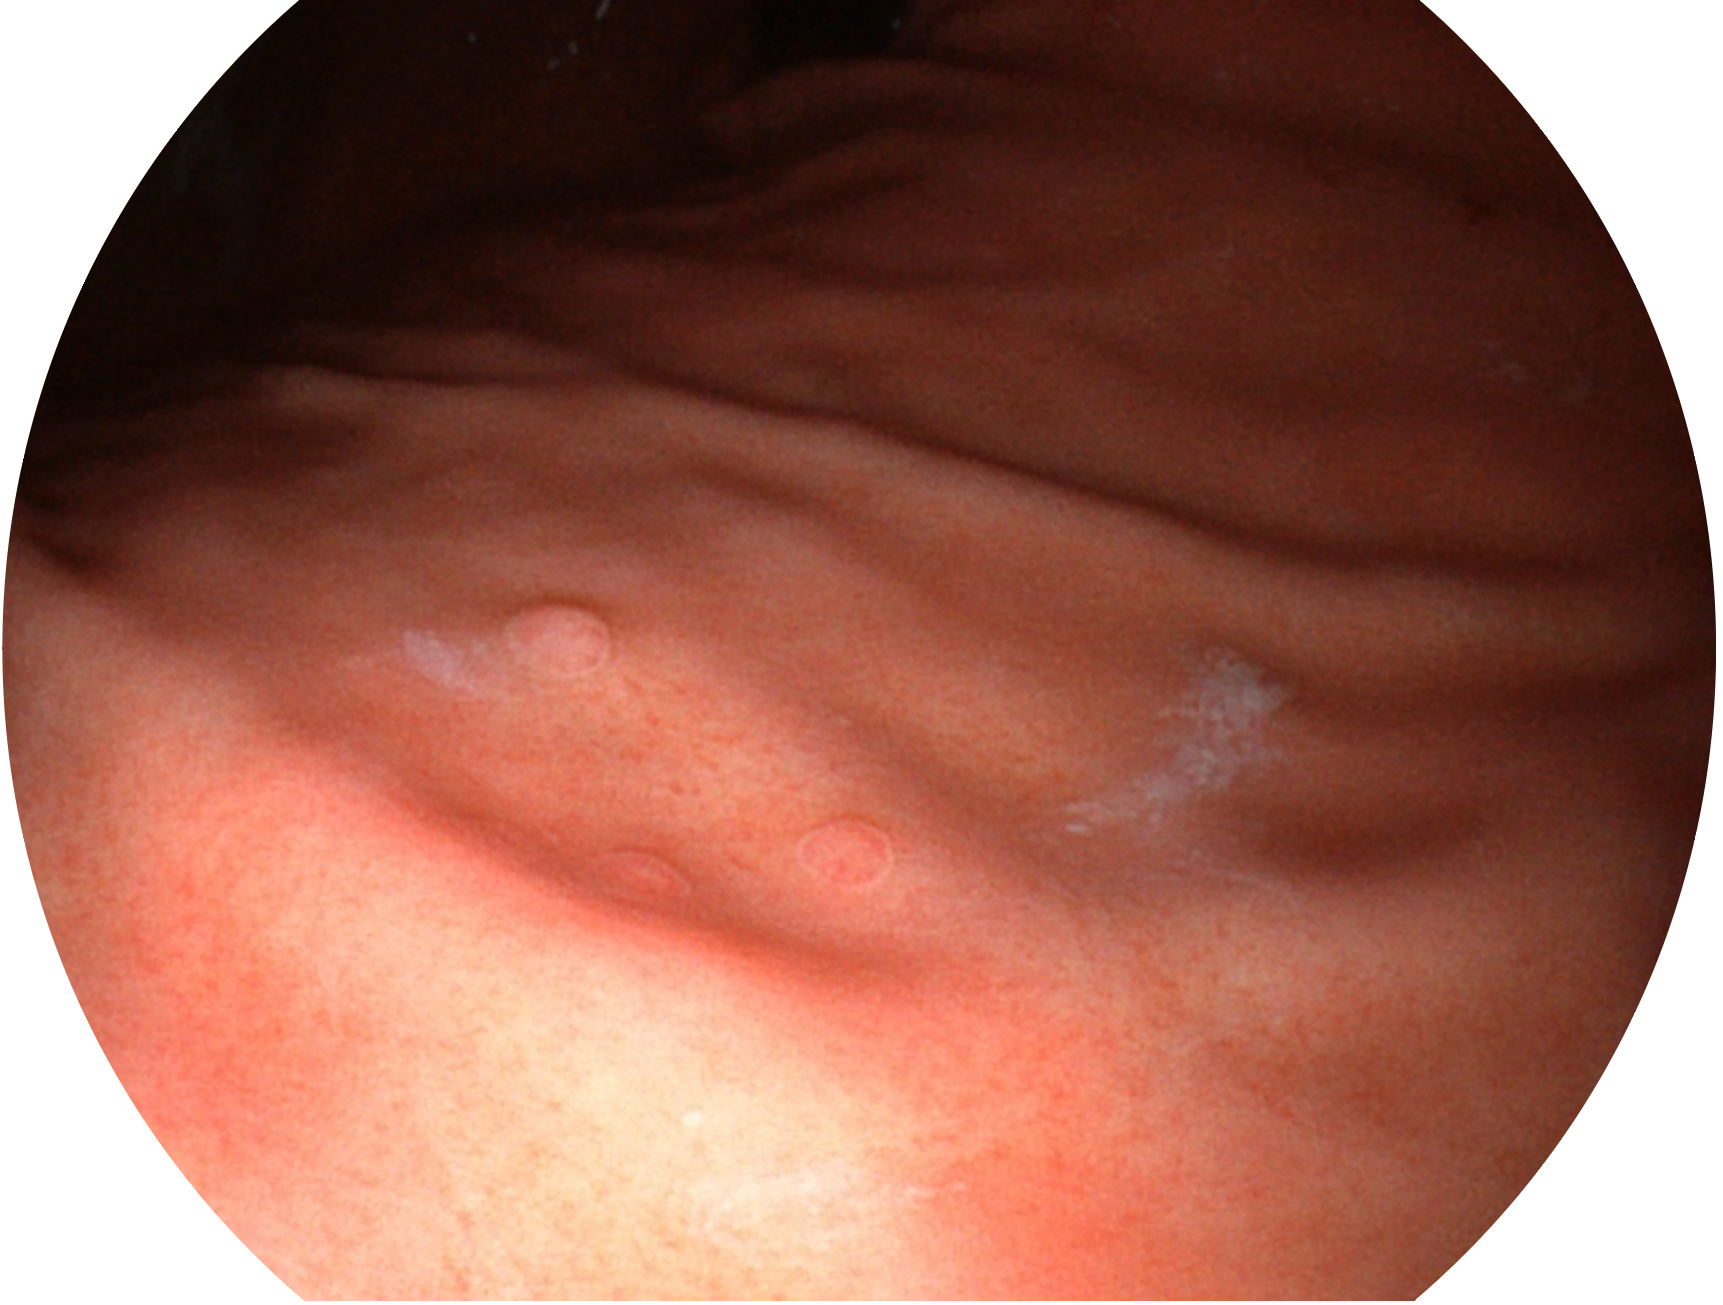

玖鼎集团新开发的内镜染色技术,主要是基于多波长LED 光源的开发,VLS-55Q 四波长LED 光源是由四个不同颜色的LED光按照相应照明模式所规定的特定发光比例进行合束后形成,合束后形成的照明光的光谱由红光、绿光、蓝光及蓝紫光这四个不同的波段范围构成。具有更高光谱自由度,通过光谱比例的控制,实现了聚谱成像技术,英文全称为“Spectral Focused Imaging, SFI”,缩写为“SFI”和光电复合染色成像技术,英文全称为“Versatile Intelligent Staining Technology, VIST”,缩写为“VIST”。